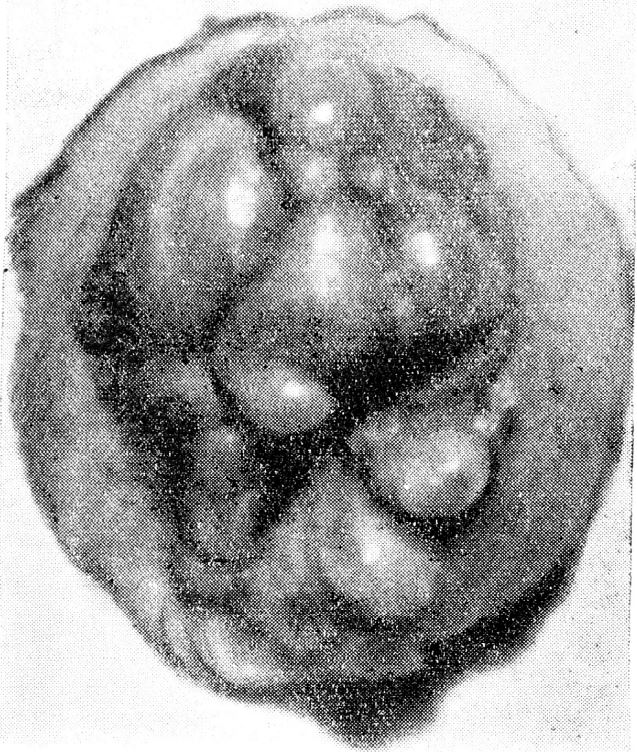

Телосложение правильное, рост выше среднего, кожа и видимые слизистые нормальной окраски. Со стороны внутренних органов патологических изменений нет. Живот мягкий, безболезненный, обильное отложение подкожной жировой клетчатки на брюшной стенке. Пупок размером 2×2 см, пигментирован — цвета темного загара, выступает над поверхностью брюшной стенки, плотный, мелкобугристый из-за полипозных разрастаний (рис. 1). При надавливании выделений нет. Влагалище рожавшей, шейка матки цилиндрическая, наружный зев закрыт. Матка в правильном положении, несколько увеличена, плотная, подвижная, безболезненная. Придатки не увеличены. Шейка чистая. Выделения белые.

Рис. 1